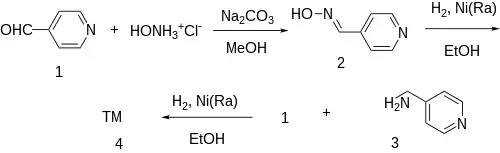

Patent:[4]

The oxime formation between isonicotinaldehyde [872-85-5] (1) and hydroxylamine gives 4-Pyridinealdoxime [696-54-8] (2). This is then reduced by catalytic hydrogenation over Raney-Nickel into 4-Picolylamine [3731-53-1] (3). Reductive amination of the last with a second equivalent of isonicotinaldehyde affords gapicomine (4).